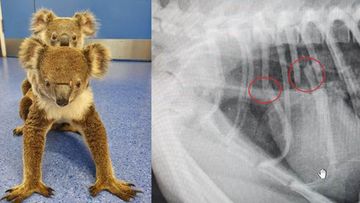

Koala On Instagram Please Share With Your Followers Meet Billy Billy Was Brought Out Of The Bushfire Zone On Koala Koala Bear Interesting Animals